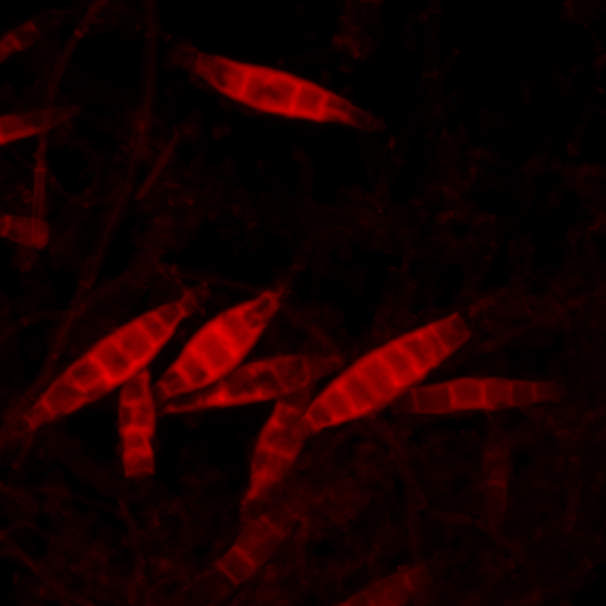

Video: What Is The Chemistry Behind Ringworm?

Video: What is the chemistry behind ringworm? phys.org

Ringworm Microscope Photos And Premium High Res Pictures - Getty Images

Ringworm Microscope Photos and Premium High Res Pictures - Getty Images www.gettyimages.co.uk

A Micrscopic Look At Ringworm - Owlcation

A Micrscopic Look at Ringworm - Owlcation owlcation.com